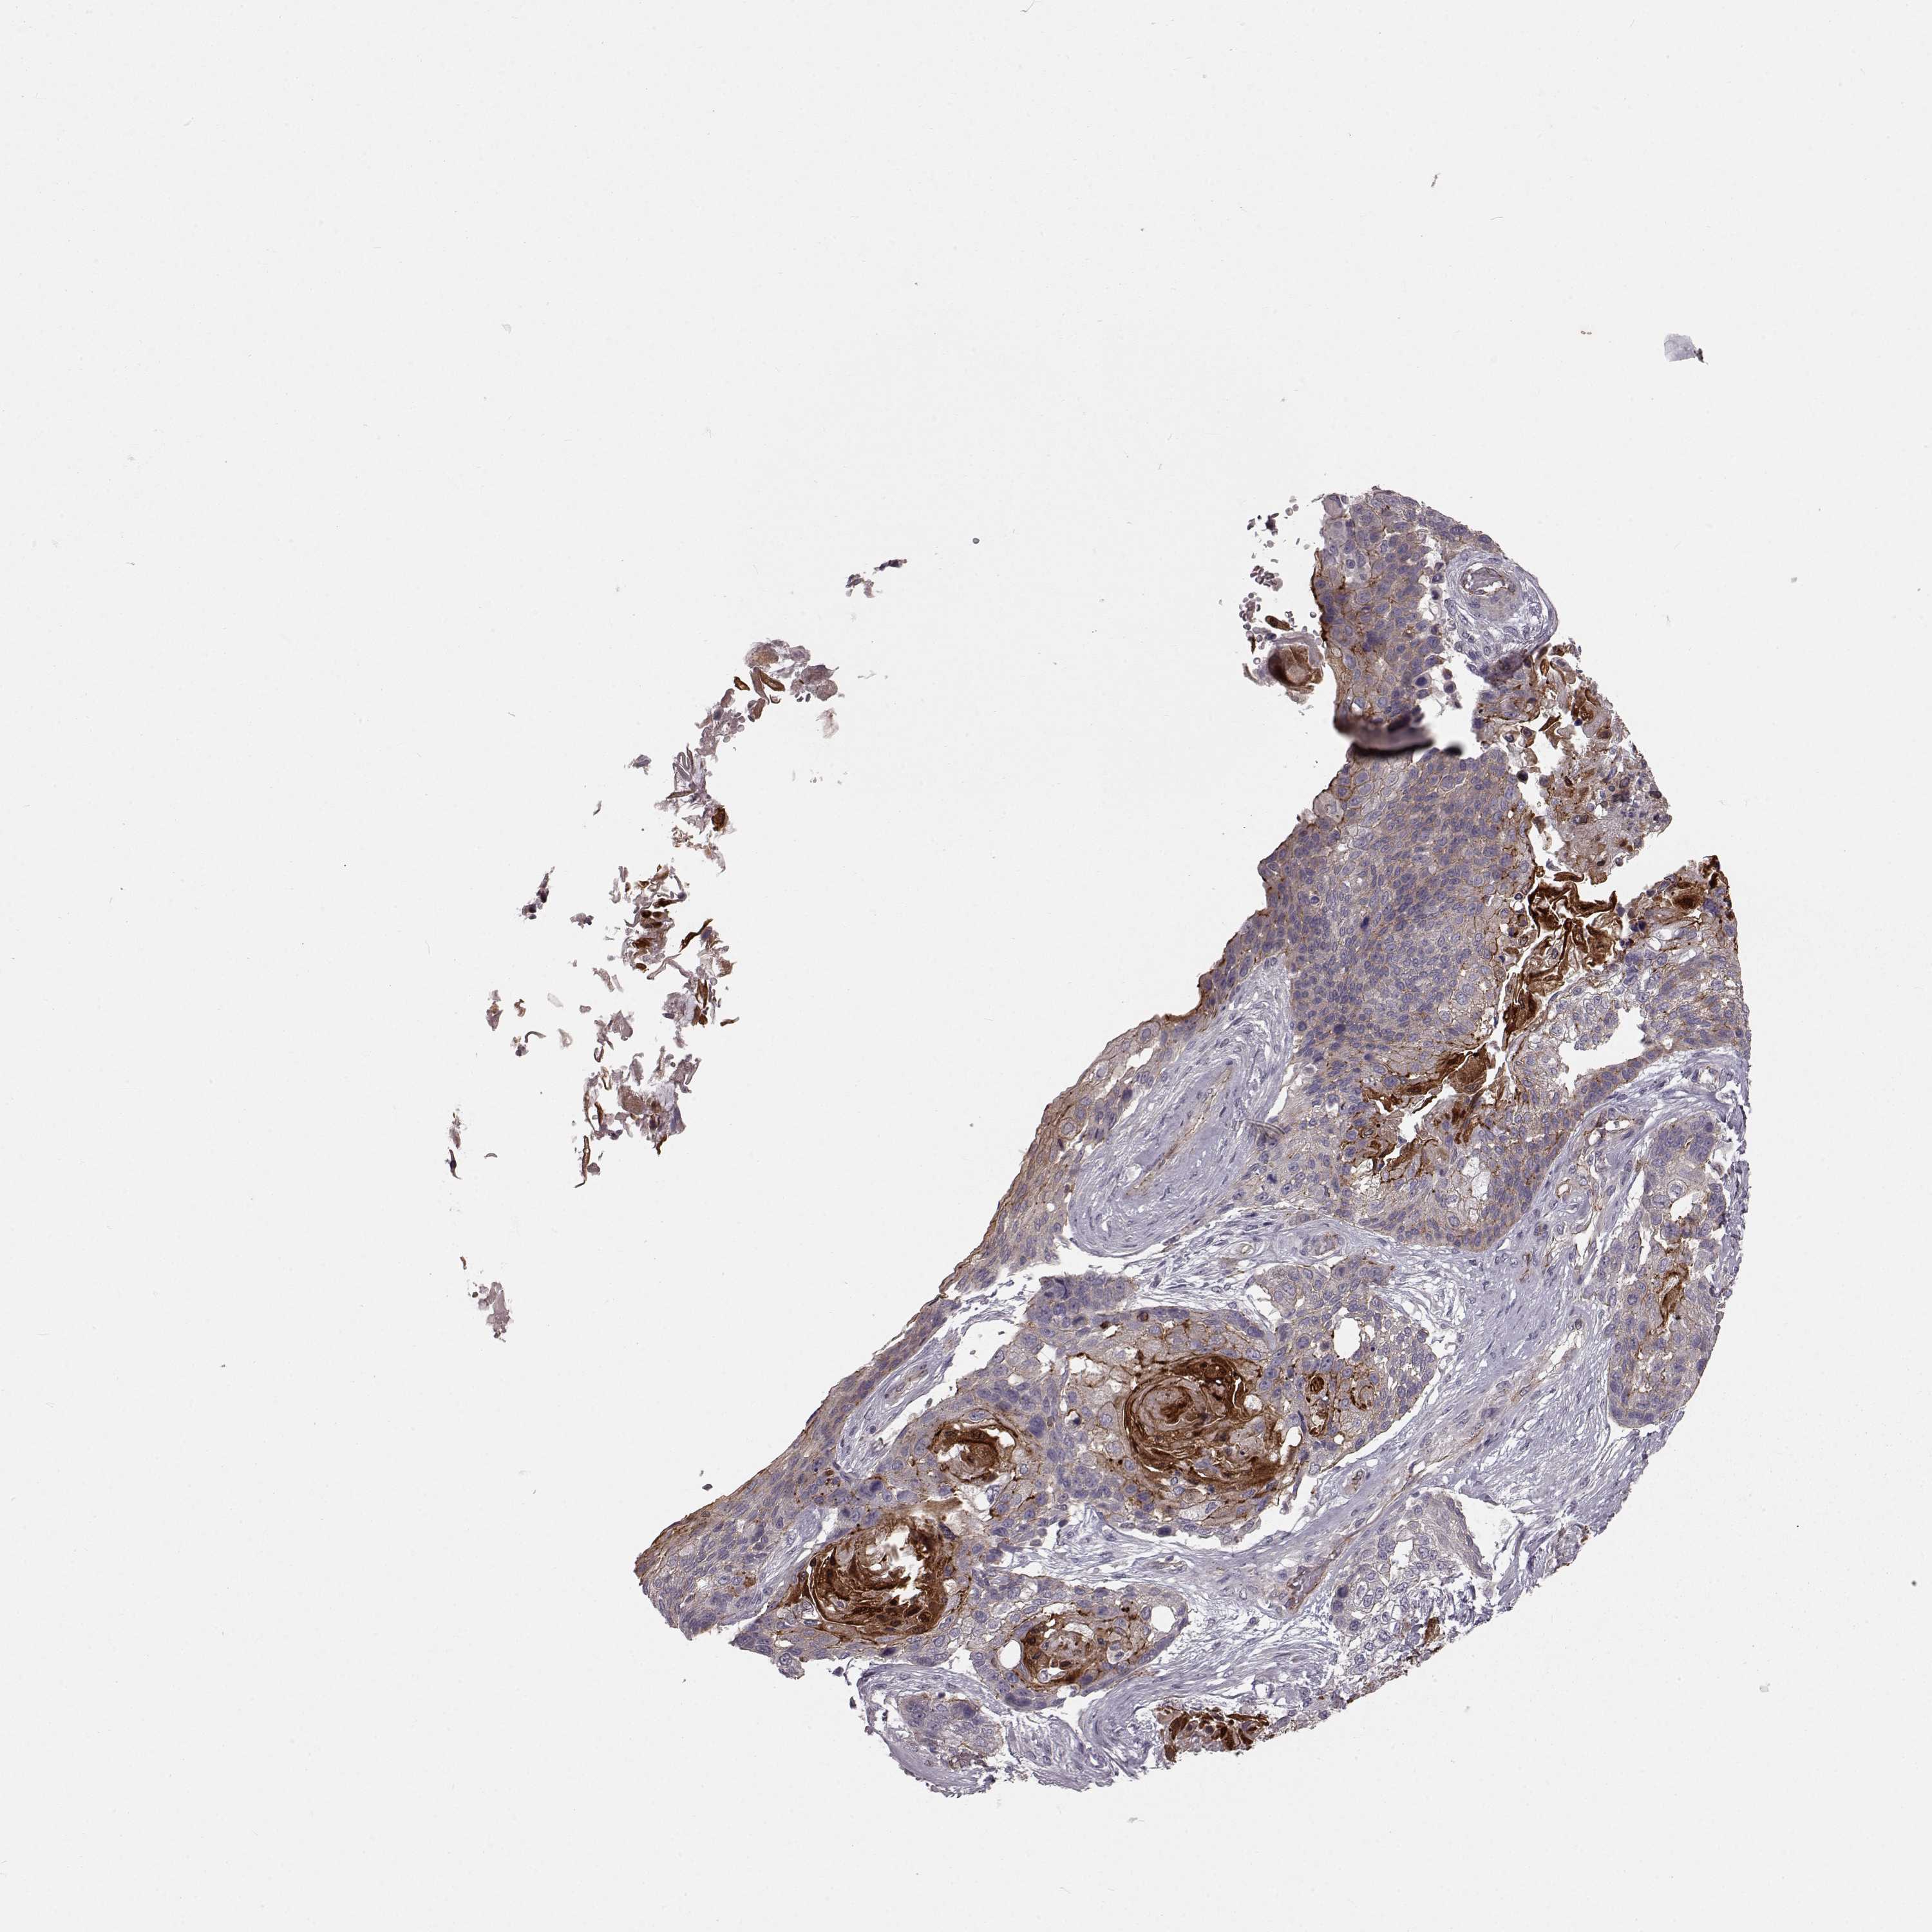

CANCER LUNG CANCER Show tissue menu

LUAD TCGA LUAD VALIDATION LUSC TCGA LUSC VALIDATION PROTEIN LUAD CPTAC PROTEIN LUSC CPTAC PROTEIN EXPRESSION

Lung cancer

Human cancer

Lung adenocarcinoma

Lung squamous cell carcinoma